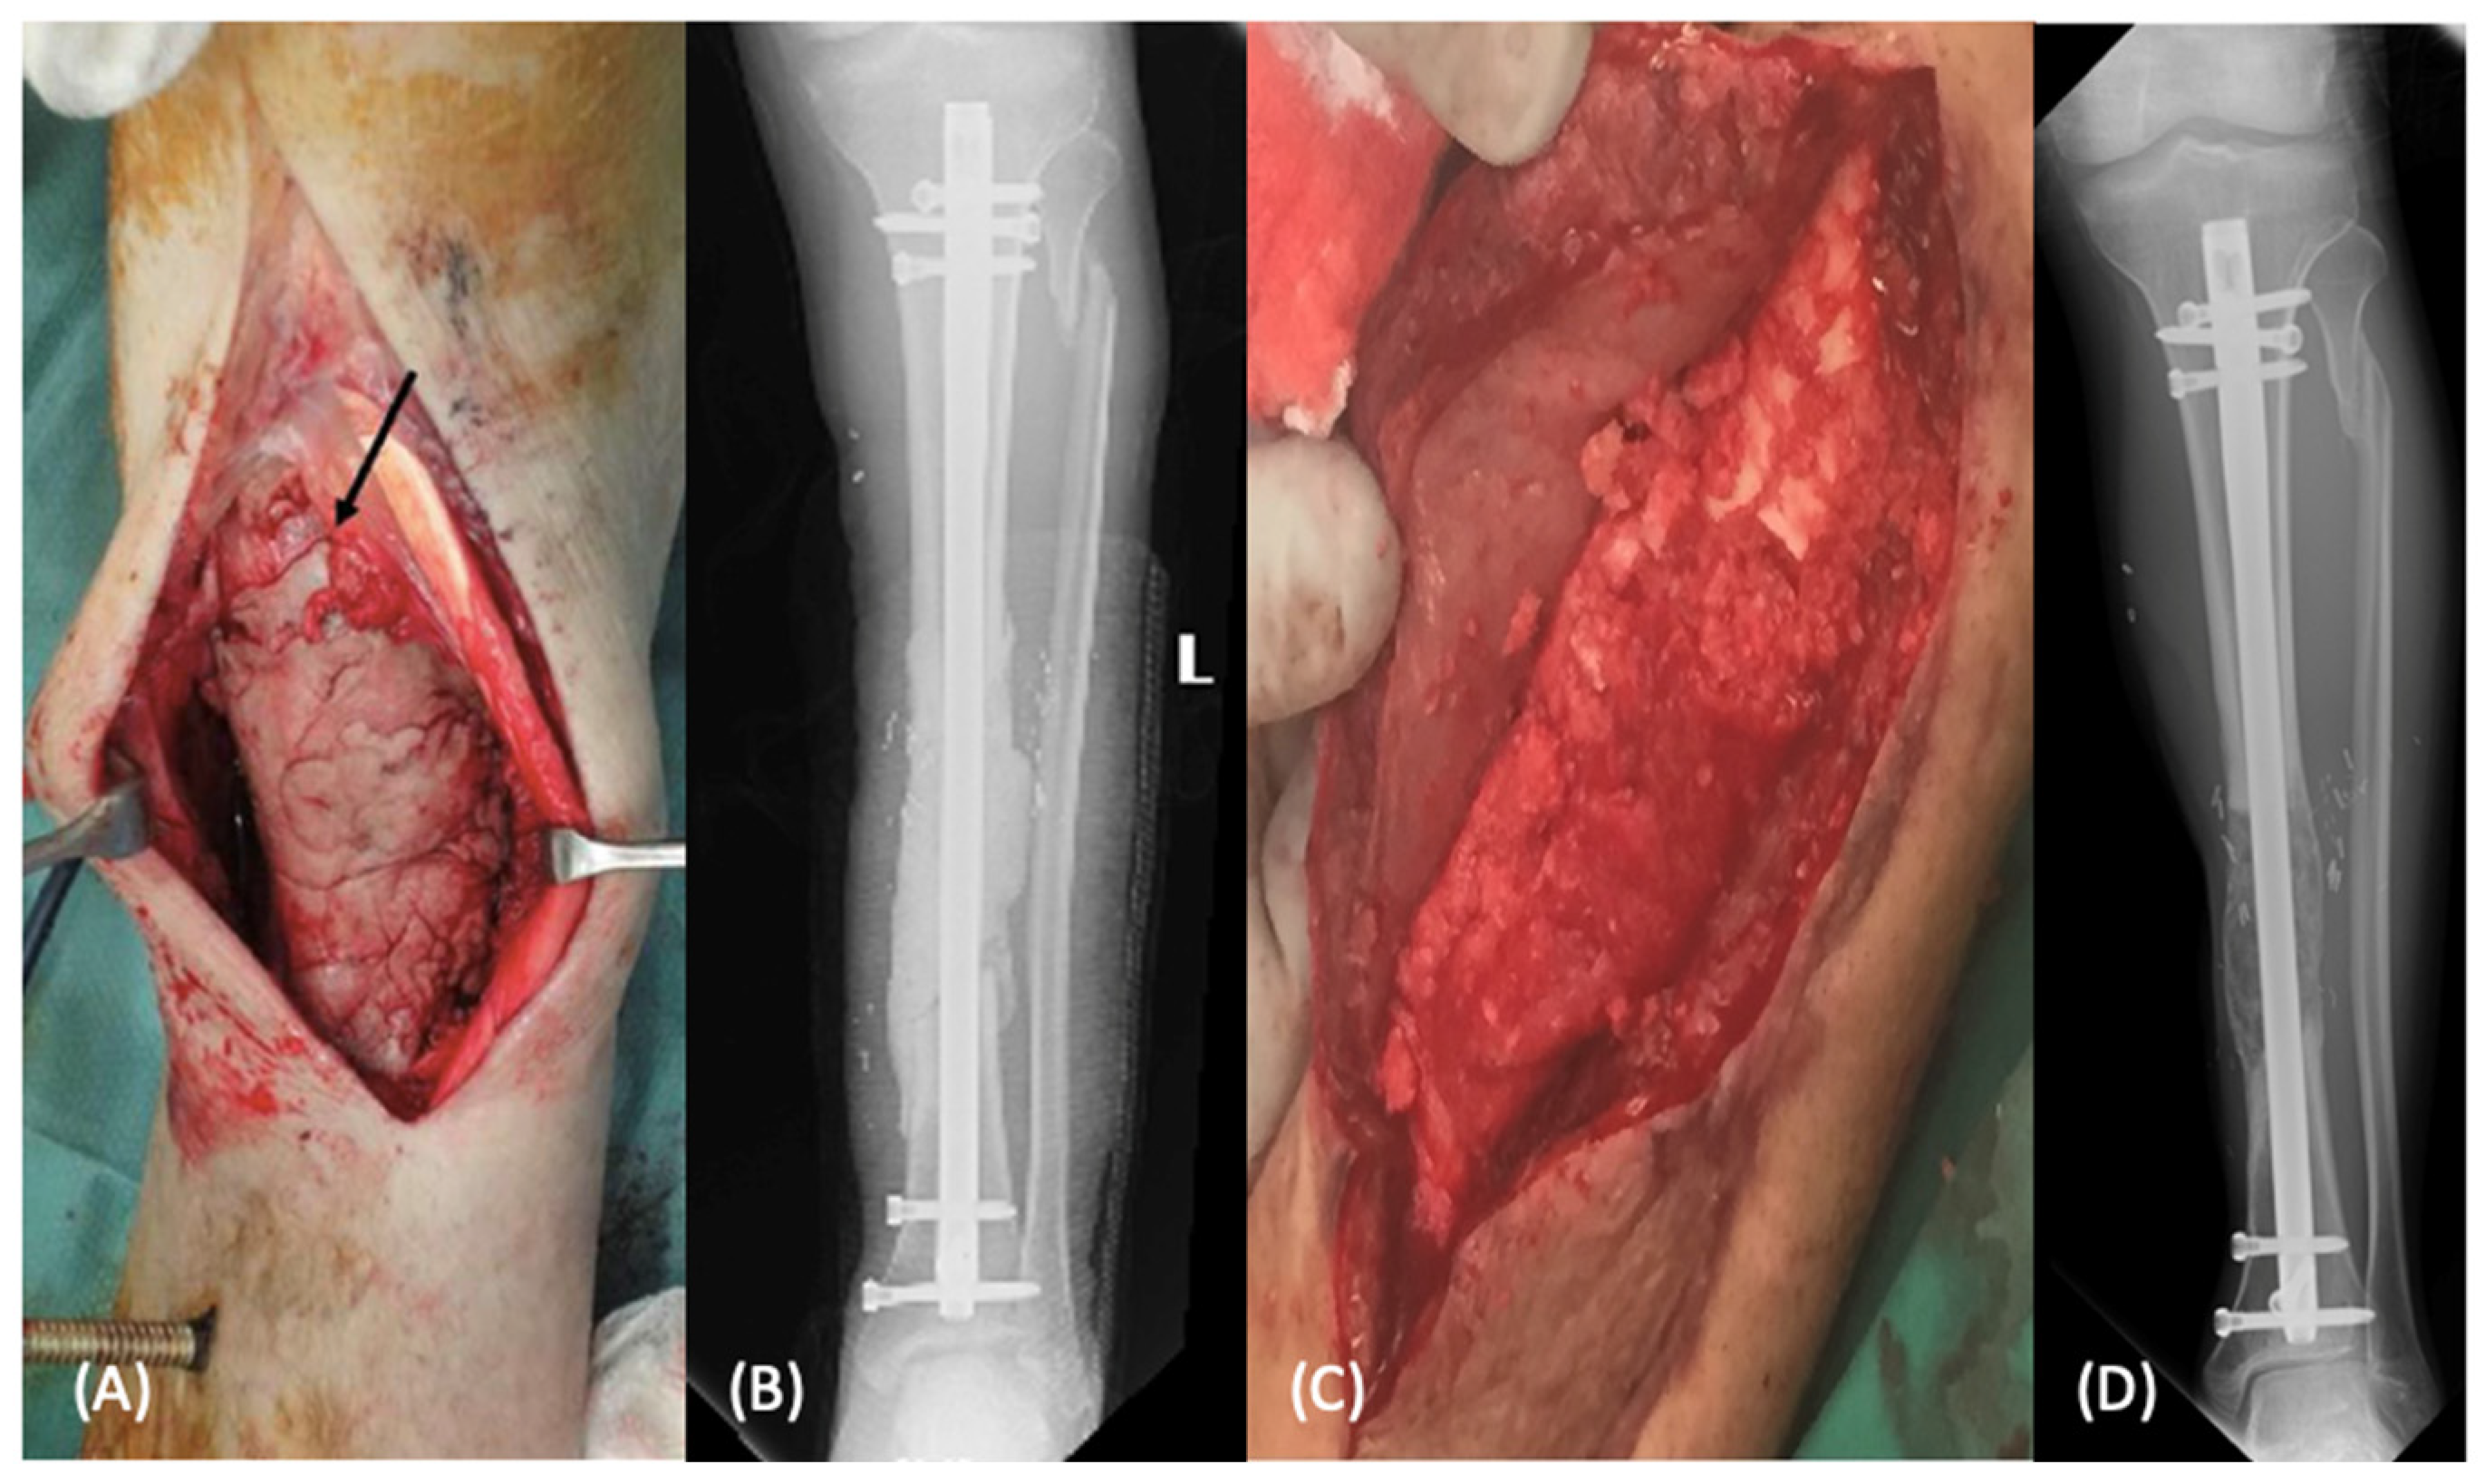

2.1.1. Induced Membrane Technique

2.1.2. Distraction Osteogenesis